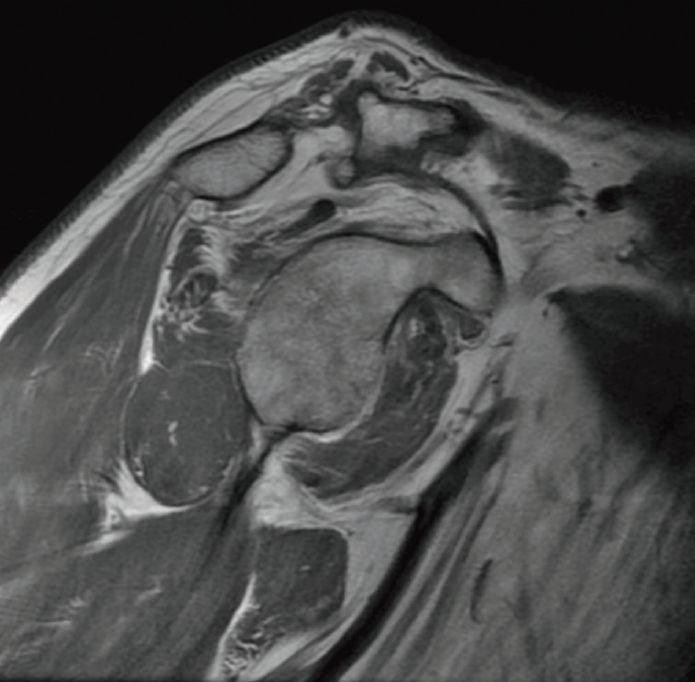

The preoperative evaluation must take a number of aspects into account, including patient age, pain, disability, functional demands and the patient expectations. In this respect, the patient must be duly informed about the expectable functional results. We also must consider other factors that can affect the surgical outcomes, such as patient comorbidities, deltoid muscle and subscapularis function, the integrity of the coracoacromial arch, the presence of arthrotic changes (Figure 1), and the need for the patient to enter prolonged rehabilitation. The main symptoms of massive ruptures of the rotator cuff are typically pain, weakness and loss of mobility(13,14). Irreparable massive ruptures are a common cause of intense pain and often prove extremely disabling for the patient. In general, patients with posterosuperior cuff rupture present reduced flexion-elevation and abduction, and total or partial loss of active external rotation(15,16). A positive external-rotation lag sign and positive hornblower sign are indicative of a deficit of the posterior cuff with the disabling of external rotation, and are associated with irreparable rupture of the teres minor and advanced fatty infiltration(17,18). The appearance of these signs at exploration is associated with poor outcomes of transfer of the latissimus dorsi(13,19). Weakness proves highly variable, and in extreme degrees we observe pseudo-paralysis. Although consensus is lacking, pseudo-paralysis in elevation could be defined as the inability to perform active flexion-elevation of 90º in the absence of nerve damage and with preserved passive mobility. External rotation pseudo-paralysis is defined as the complete loss of active external rotation strength in the presence of unrestricted passive external rotation and the absence of neurological lesions. Some authors consider pseudo-paralysis to be a contraindication to transfer of the latissimus dorsi(20), and is seen to be associated with poor outcomes, since it does not afford the necessary strength to overcome a pseudo-paralytic shoulder and achieve postsurgical elevation(12). Most authors agree that the deltoid muscle must be in good condition in order to perform transfer(21). Irreparable rupture of the subscapularis is an absolute contraindication to this kind of transfer, due to anterior escape of the humeral head when the deltoid muscle contracts in the absence of the subscapularis(9). However, good results can be obtained in partial ruptures of the upper third of the subscapularis that can repaired in the same surgical step(21)(Figures 2 and 3).